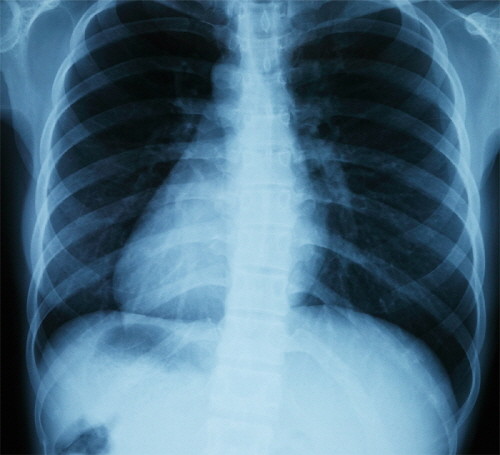

| ▲ 사진제공: 예담정형외과 | ||